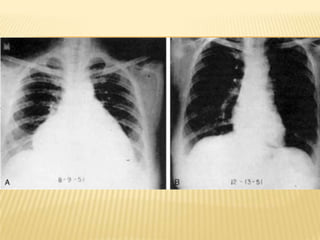

HIPOTIROIDISMO CONGENITO Niña de 17 años

Diagnosticada al nacer

No recibió tratamiento

Puente nasal pobremente desarrollado

Hipertelorismo

Orejas anchas y mas grandes a los apropiado para su tamaño de cabeza

Macroglosia

Extremidades cortas respecto al troncoKliegman: Nelson Textbook of Pediatrics, 18th ed.

Fontanelas abiertas

Suturas sin fusionar

Dientes “de leche” y permanentes presentes

Centros epifisiarios sin crecimiento

Ausencia de epífisis radial distal

Edad ósea estimada de 9 mesesKliegman: Nelson Textbook of Pediatrics, 18th ed.